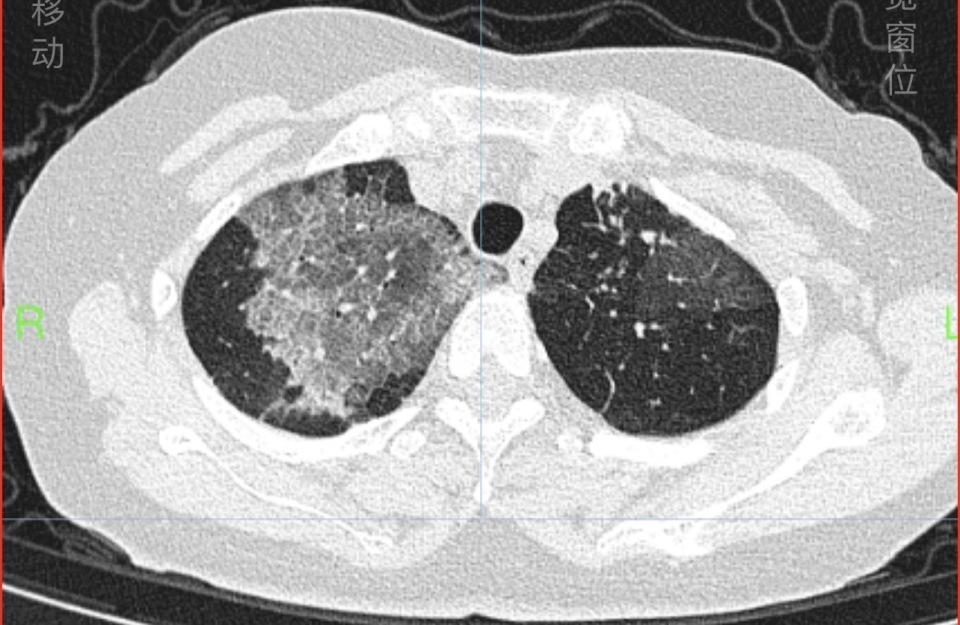

63岁的戴女士被诊断为重度过敏性哮喘多年,平时规律接受哮喘治疗,控制得不错。但近4天来,她出现发热、喘息发作厉害,夜间憋闷不能入睡,于是赶紧到湖南省人民医院呼吸内科检查,发现双肺大片磨玻璃及网格样炎症病变。

△戴女士入院时肺部CT显示双肺大片磨玻璃及网格样炎症病变(上图),治疗一周后的肺部CT如下图